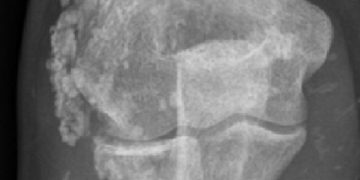

Yavru Zarlarında Metaplastik Kemikleşme, yavru zarlarındaki hücre metaplazisinden kaynaklanan çekirdekli osteoklastik tipte hücreler içeren, genellikle domuzlarda görülen kemikleşmedir. Metaplastic placental ...